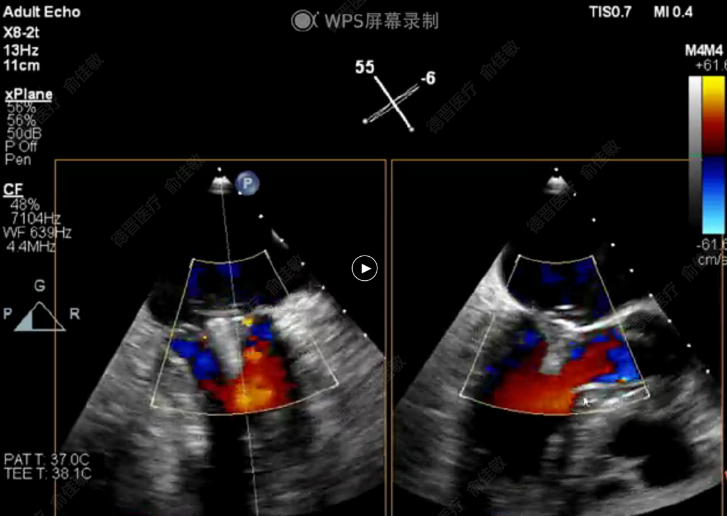

2021年8月27日,武汉大学人民医院江洪教授、陈静教授及超声科周青教授与浙江大学附属第二医院王建安教授团队密切合作,应用中国第一款自主研发的DragonFly经导管二尖瓣瓣膜夹系统,成功为一位高龄患者完成了经导管二尖瓣缘对缘修复手术。期间与美国弗吉尼亚大学医学中心David Scott Lim教授团队及香港亚心医院林逸贤教授全程视频连线沟通,团队通力合作,为患者早日康复尽心竭力。